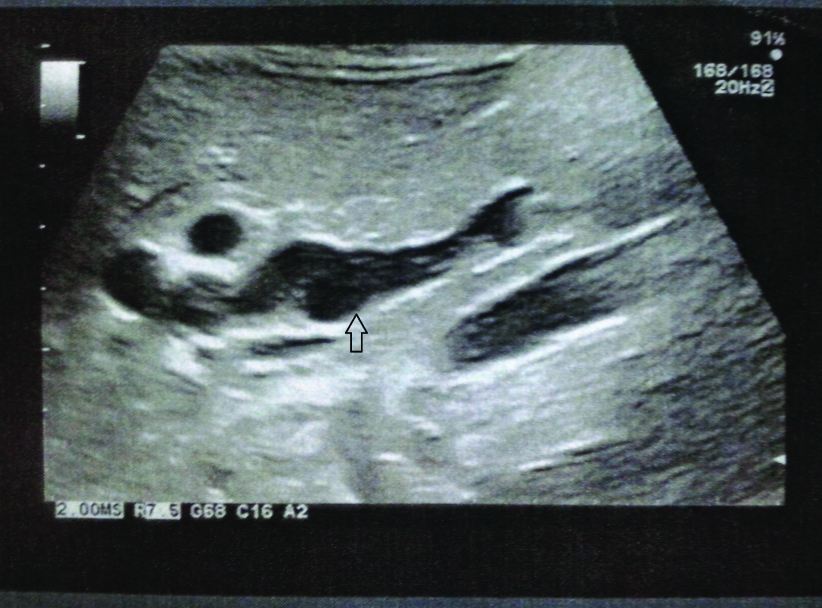

Follow-up ultrasound investigation that was performed after three months, which revealed a saccular lesion adjacent to the distal 1/3 of the bile duct measuring approximately 18mm in diameter and bile sludge that was detected along the common bile duct [Table/Fig-1]. Intra and extra hepatic bile ducts were measured within the upper limits of normal diameter. Subsequent Magnetic Resonance Cholangiopancreatography (MRCP), revealed a cystic lesion of (or adjacent to) the bile duct without identification of a foolproof Abnormal Pancreatic Biliary Duct Junction (APBDJ). Other MRCP findings included mild dilatation of the common hepatic duct and the left and right hepatic ducts without any stones or sludge. Interestingly, gall-bladder and cystic duct were not depicted [Table/Fig-2].

Ultrasonography revealing a saccular lesion adjacent to the distal 1/3 of the bile duct (arrow).